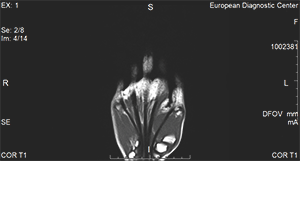

Анатомия кисти рук, что показывает МРТ, магнитно-резонансная томография

Сложное анатомическое строение отличает кисть, состоящую из большого количества костей и суставов, сложной системы сухожилий, связок и мышц, благодаря чему реализуется мелкая моторика.

МРТ кисти руки позволяет врачу оценить:

• Суставные щели и хрящи, суставные поверхности;

• Запястно-пястные суставы;

• Пястно-фаланговые суставы;

• Межфаланговые суставы;

• Сухожилия сгибателей и разгибателей пальцев;

• Мягкие ткани кисти рук.